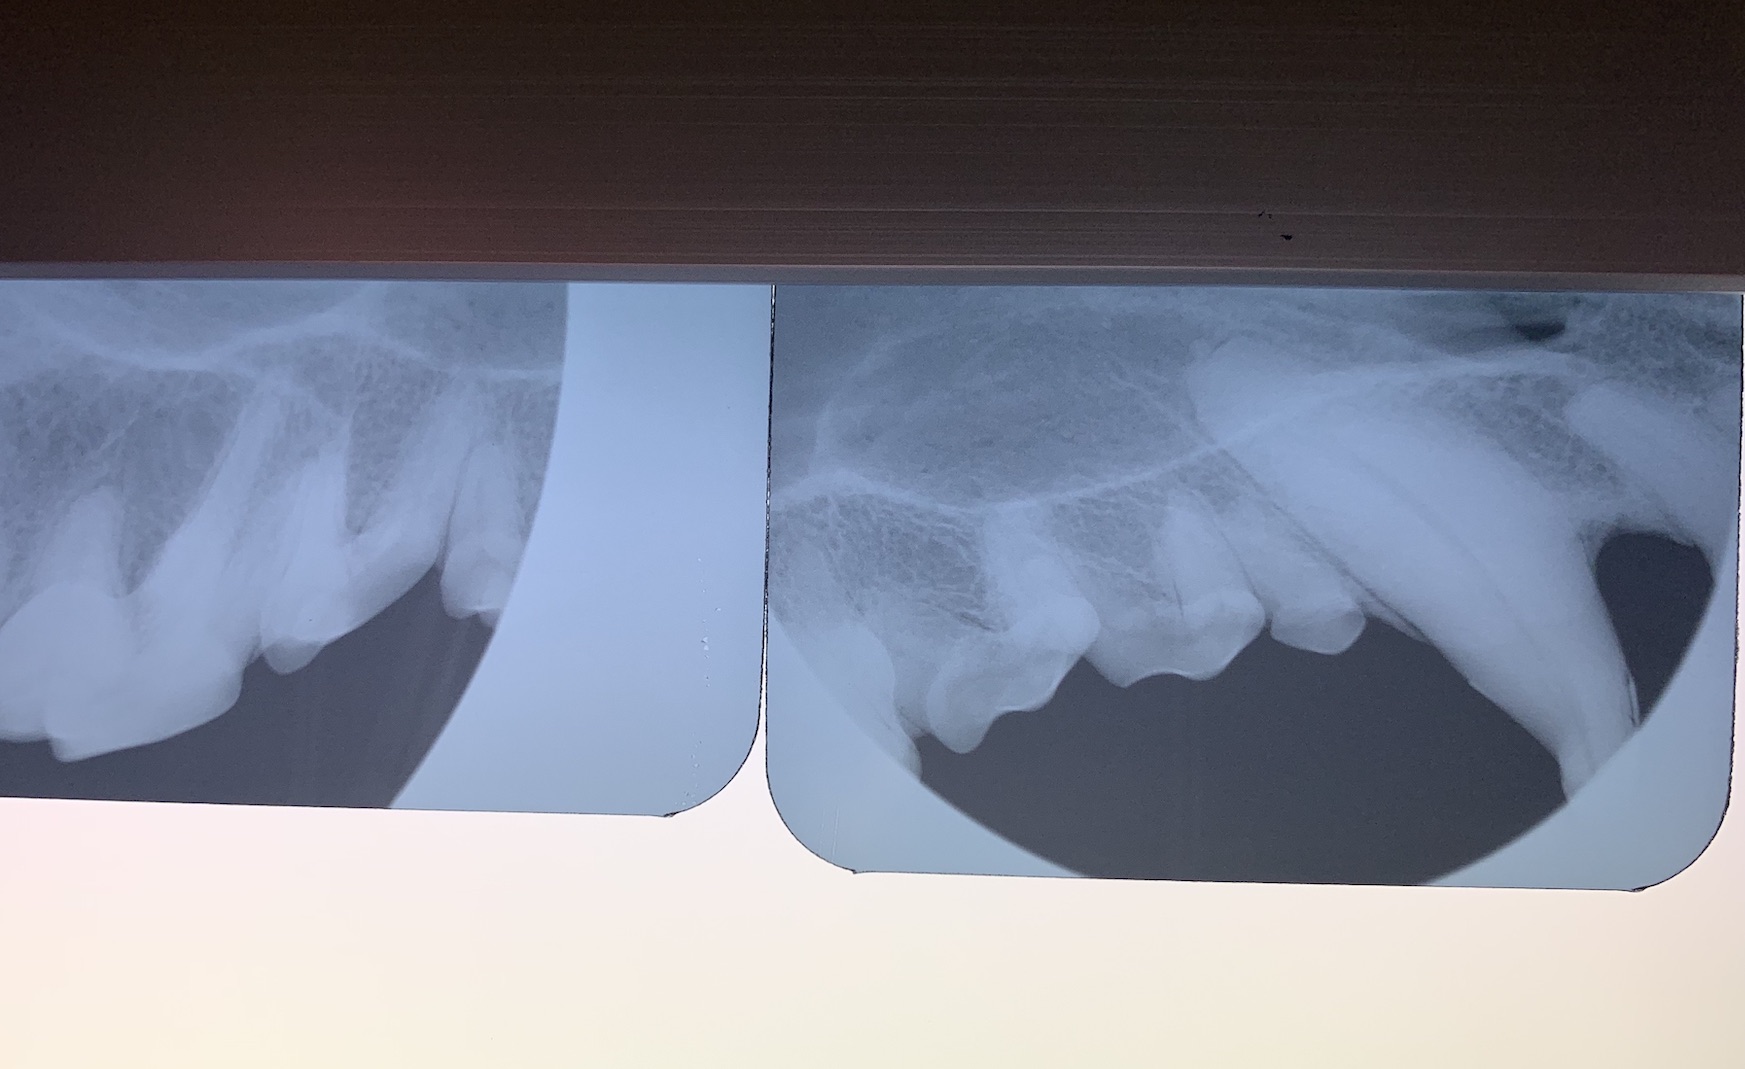

↑ 実習では歯科専用のX線撮影についても学んだとのことです。一般診療で使われる通常のX線装置と比較し、歯科専用のX線撮影装置では照射野が狭く、撮影角度の設定も特殊で特別な技術が必要です。歯科専用X線装置では、歯髄や歯根周囲の構造が詳細に読影可能となります。